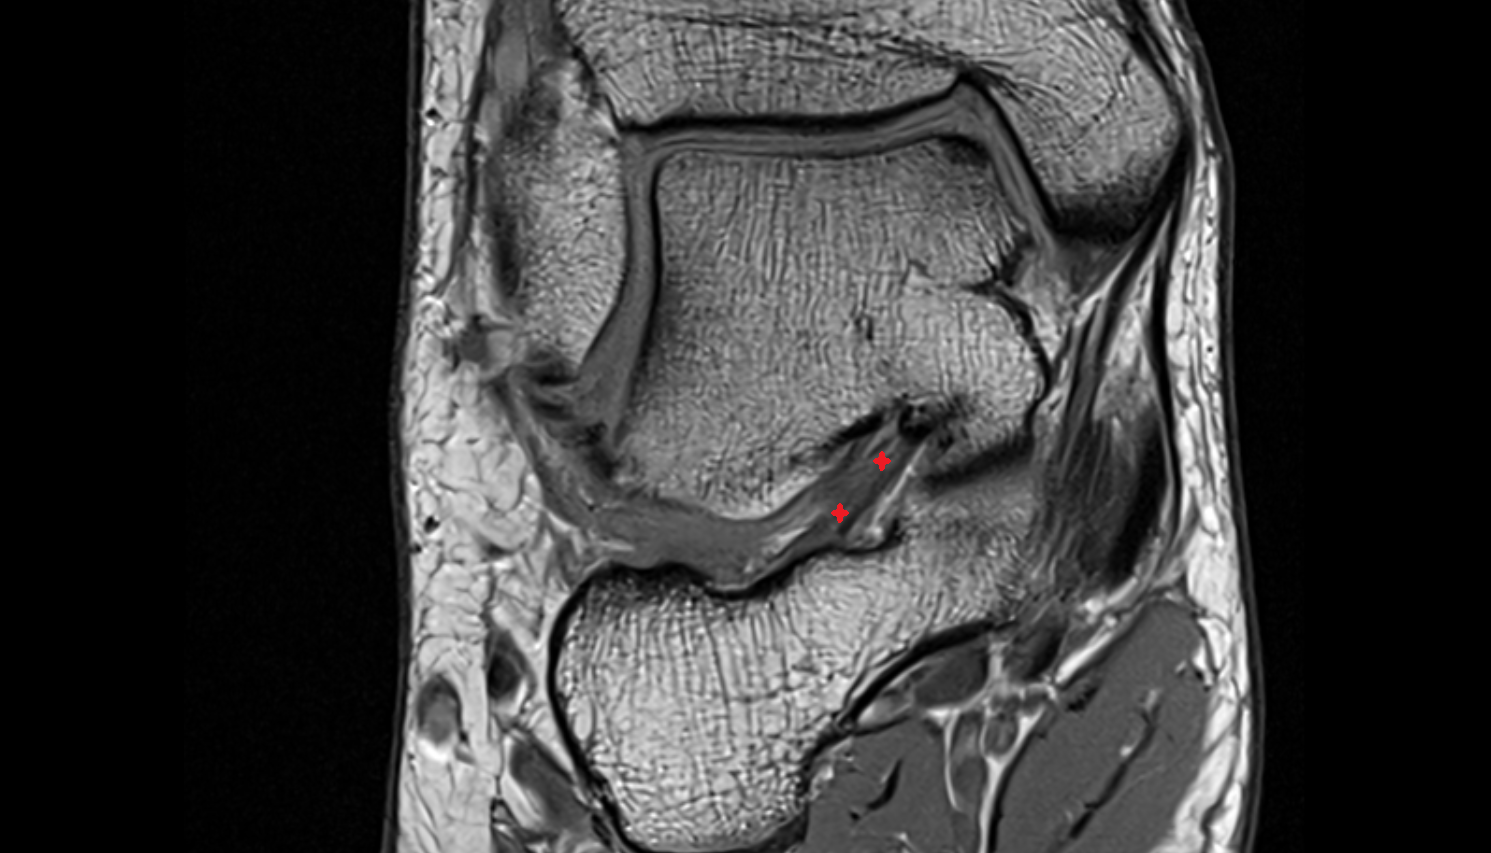

- Medial meniscus

- Lateral meniscus

- Anterior horn of medial meniscus

- Posterior horn of medial meniscus

- Body of medial meniscus

- Anterior horn of lateral meniscus

- Posterior horn of lateral meniscus

- Body of lateral meniscus